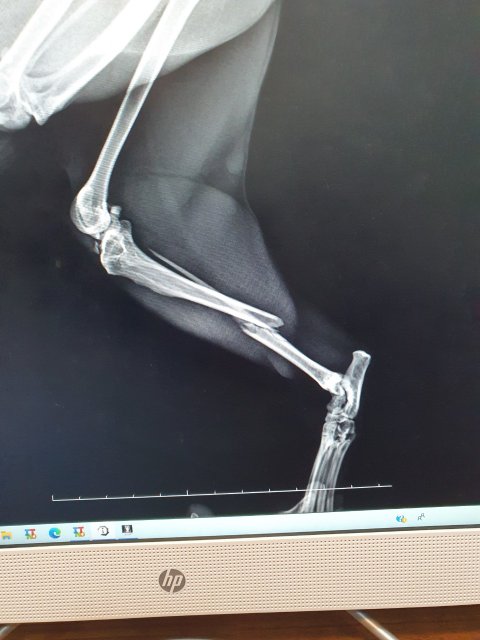

- 왼쪽 뒷다리 탈구, 관절염

그런데 송이가 내려오는 착지 과정에서 잘못됐는지 몇시간이 지나서 아팠던 다리가 부러진 듯 아예 못쓰는 상황이었고 오늘 캣맘분이 병원에 데려가셨는데 심하게 골절되어 당장 수술하지 못하면 다리를 절단해야하는 상황이에요.